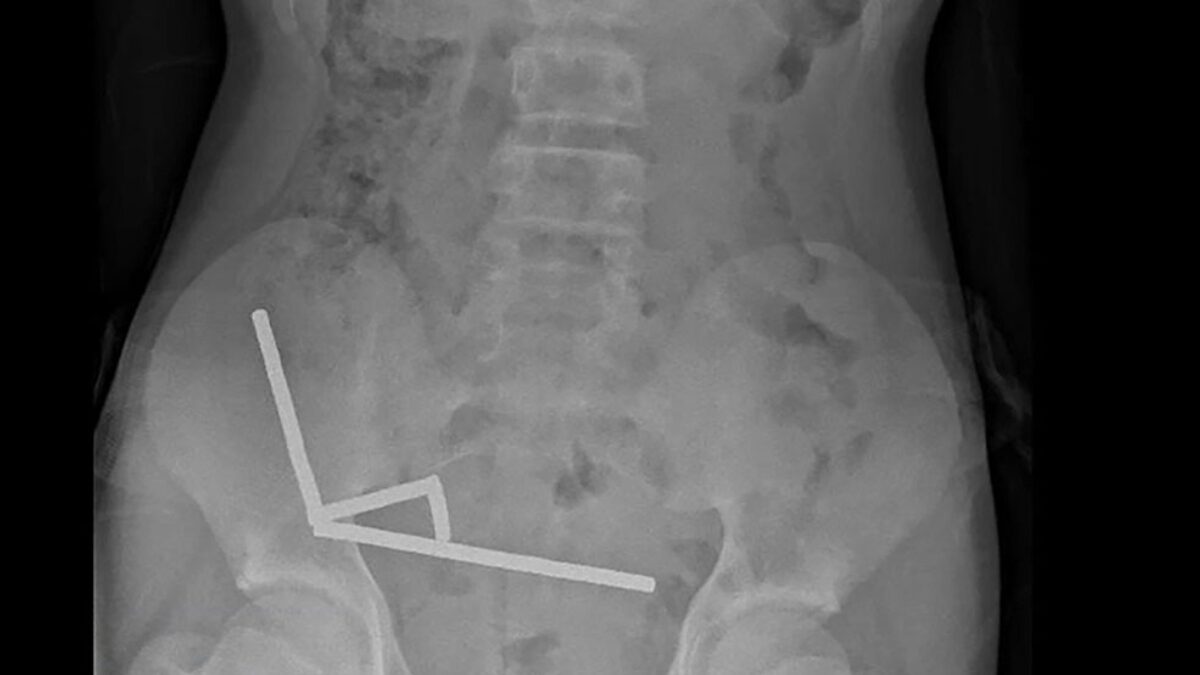

Η ακτινογραφία έδειξε ότι οι μαγνήτες είχαν συγκεντρωθεί σε τέσσερις ευθείες γραμμές μέσα στα έντερα του παιδιού, όπως φάνηκε και στην ακτινογραφία.

«Φαινόταν ότι βρίσκονταν σε διαφορετικά σημεία του εντέρου, τα οποία είχαν κολλήσει μεταξύ τους λόγω των μαγνητικών δυνάμεων», αναφέρει η έκθεση.